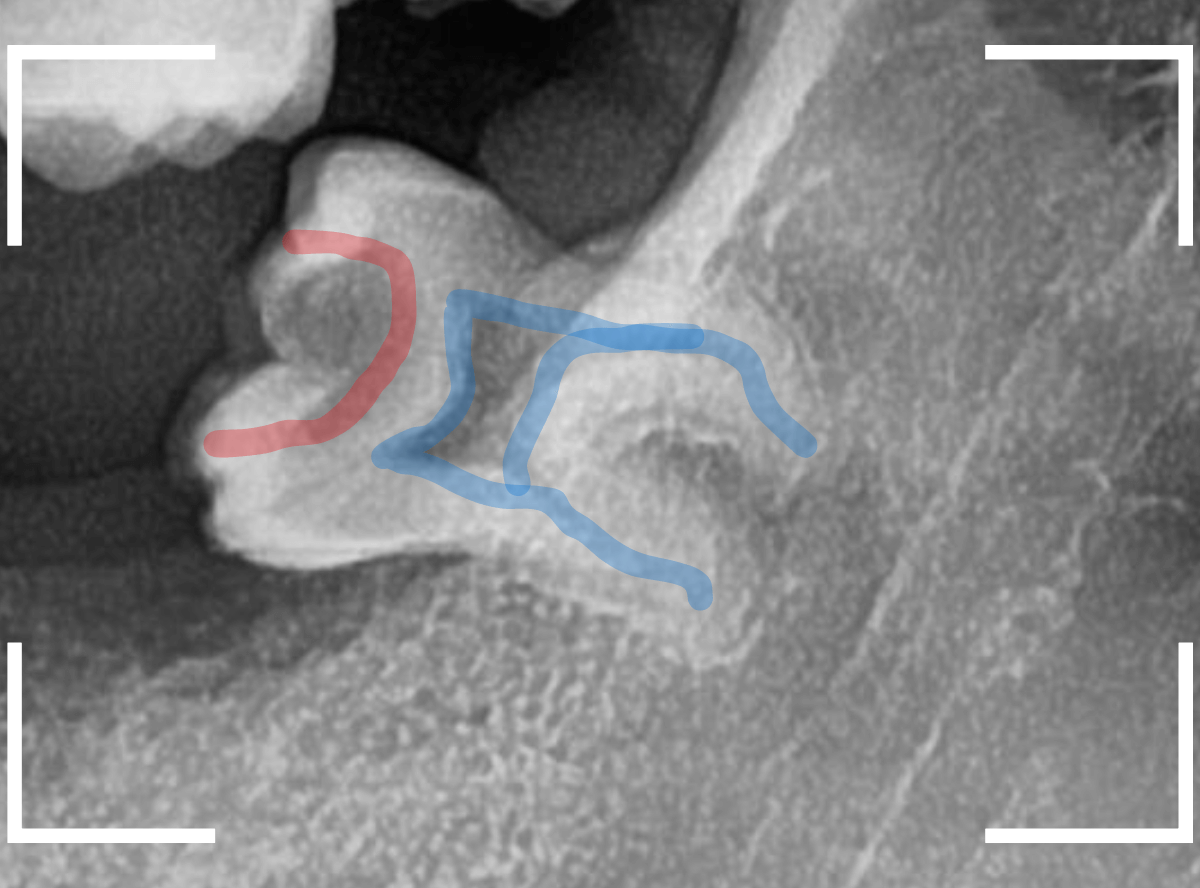

ここでは、比較的簡単なおやしらずの抜歯の例を中心にご紹介します。

このようなおやしらず、あなたはありませんか?